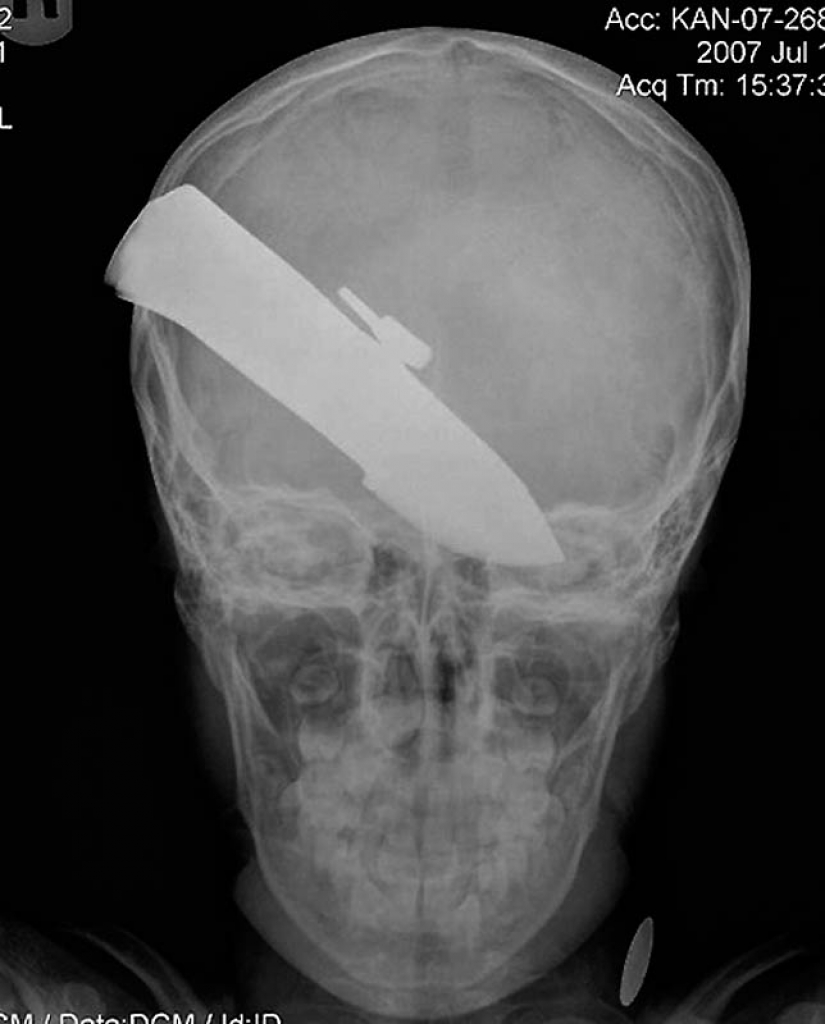

15. Knife in the head 10 year old boy. The boy survived.

18. 12-centimeter knife in the skull of a teenager.